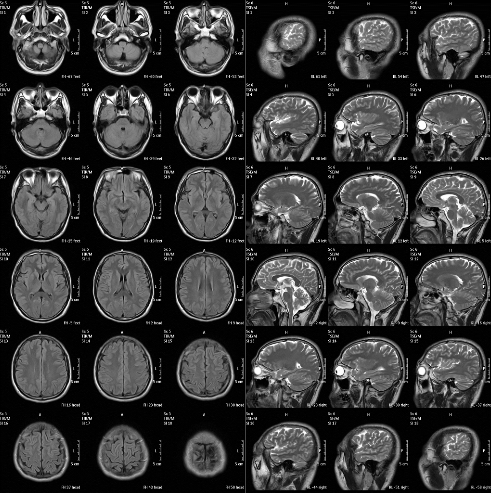

MRI(核磁)头部影像图

方案介绍

MRI(核磁)头部影像图是一种通过磁共振成像技术获得的头部图像,它利用磁场和射频脉冲使人体组织中的氢质子发生共振,进而产生信号,通过计算机处理这些信号生成图像。MRI头部影像图在医学诊断中具有重要地位,特别是在颅脑疾病的诊断中发挥着关键作用。